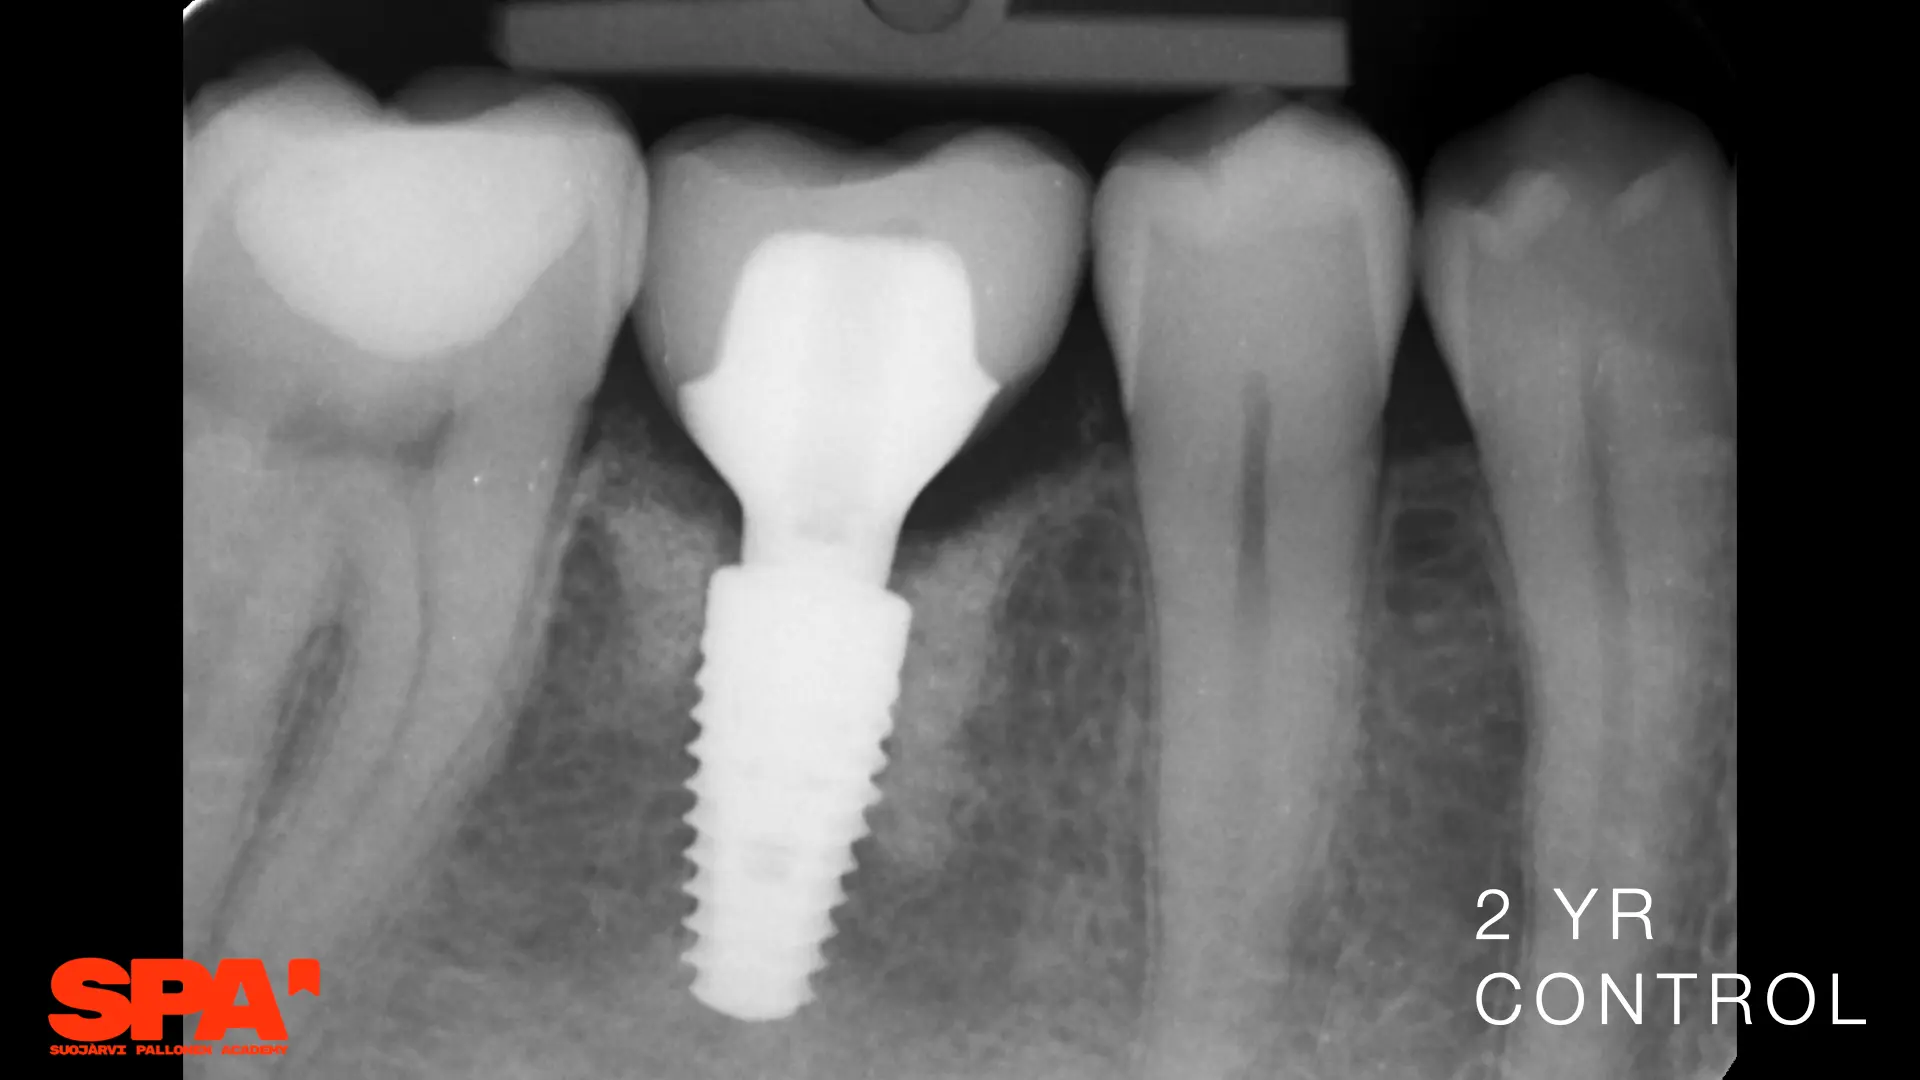

Seminaariesitykset keskittyvät täysin synteettiseen EthOss-biomateriaaliin, joka on kehitetty edistämään potilaan omaa luun uudistumista hammasimplanttien ja suukirurgian yhteydessä. EthOss koostuu β-trikalsiumfosfaatista ja kalsiumsulfaatista, jotka luovat ihanteelliset olosuhteet luun kasvulle ilman sulamattomia vieraspartikkeleita tai eläinperäisiä aineita, korvautuen kokonaan elävällä isäntäluulla noin 6–12 kuukaudessa.

Esityksissä käsitellään materiaalin valmistelua, käyttöä luusiirteissä sekä kliinisiä tuloksia, kuten nopeaa luunmuodostusta (jopa 50 % uutta luuta 12 viikossa), ilman tarvetta erilliselle kollageenikalvolle.

This lecture will explore how surgical simplicity combined with biologically active materials can achieve outstanding results across a range of indications — from socket preservation and regeneration to sinus lifting. Through clinical cases and practical protocols, Dr. Stuart Kilner will demonstrate how to optimise handling, improve efficiency, and achieve stable regeneration by working with, not against, the body’s innate capacity to heal.

EthOss cases by Dr Stuart Kilner

EthOss cases by Dr Ilkka Pallonen